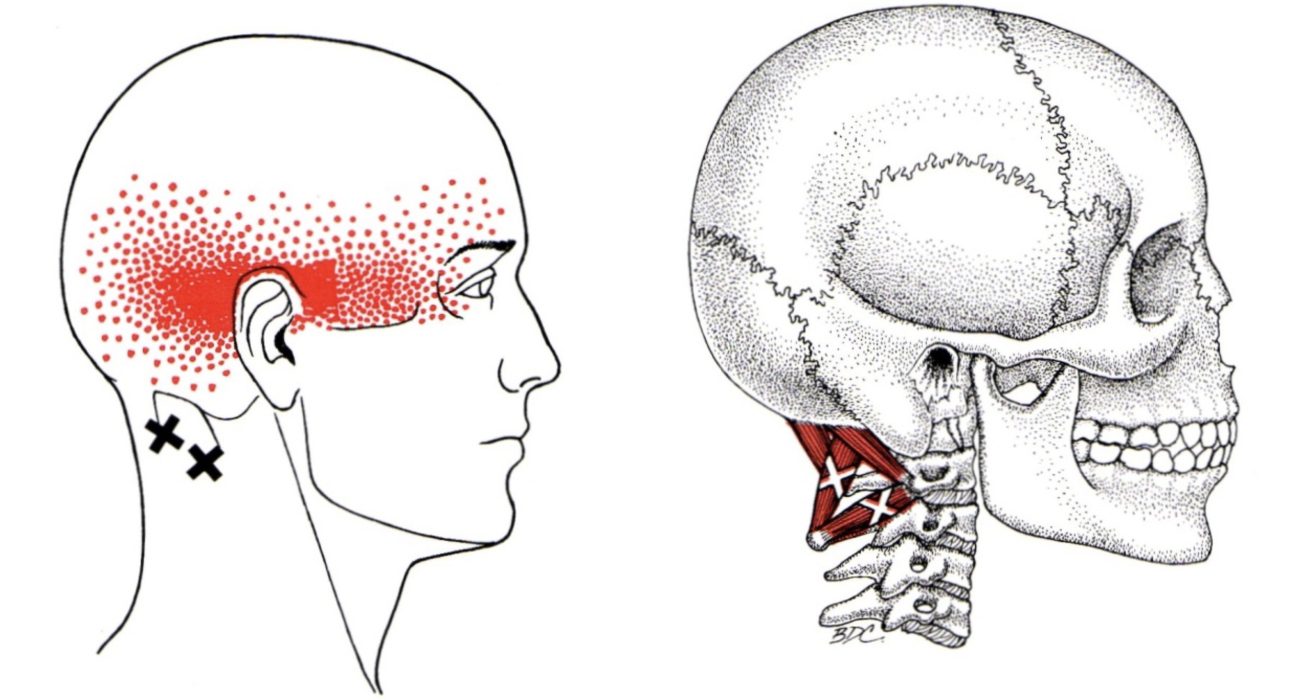

سردرد ناشی از دیسک گردن

سردرد ناشی از دیسک گردن معمولاً به دلیل فشار روی اعصاب گردن یا گرفتگی عضلات گردنی ایجاد میشود. این درد معمولاً از پشت سر شروع میشود و به شقیقهها یا حتی پشت چشمها انتشار پیدا میکند. برای کاهش درد، این کارها رو امتحان کن: درمانهای خانگی و سبک زندگی سردرد ناشی از دیسک گردن: 🔹 […]

سردرد گردنی

سردرد گردنی (Cervicogenic Headache – CGH) نوعی سردرد است که منشأ آن مشکلات و اختلالات در گردن (ستون فقرات گردنی) میباشد. این سردرد معمولاً از گردن یا قسمت پشت سر شروع شده و به سمت جلو، شقیقهها و حتی پشت چشم گسترش پیدا میکند. دلایل سردرد گردنی سردرد گردنی معمولاً به دلیل مشکلاتی در ستون […]